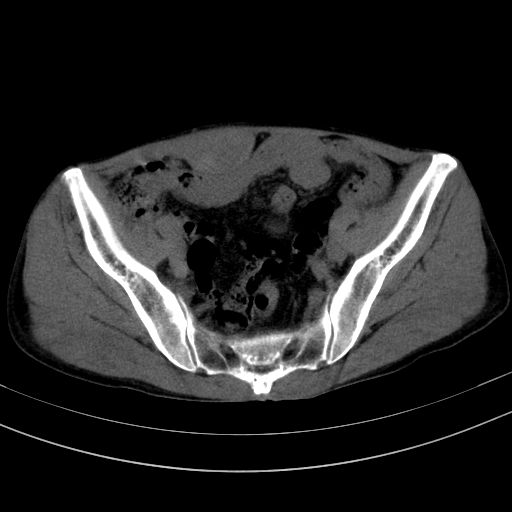

以下是引用37度在2010-1-9 14:37:00的发言:[br]1.双肾囊肿,左肾积水结石,.胆总管轻度扩张;[br]2.病灶在腹膜外,考虑纤维瘤。

以下是引用dyqct在2010-1-9 17:56:00的发言:[br]考虑:1.双肾囊肿,左肾积水结石、旋转不良。[br] 2.右侧腹直肌血肿或纤维瘤。[br]肠道准备不好。做个增强。